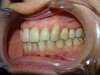

Avant

Intrabuccale droite - Avant traitement 1 (09-05-2022) - 3